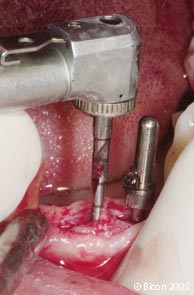

23. |

平行杆插入种植窝内确定其方向位置,并作为下一个牙槽窝预备方向的参考。 |